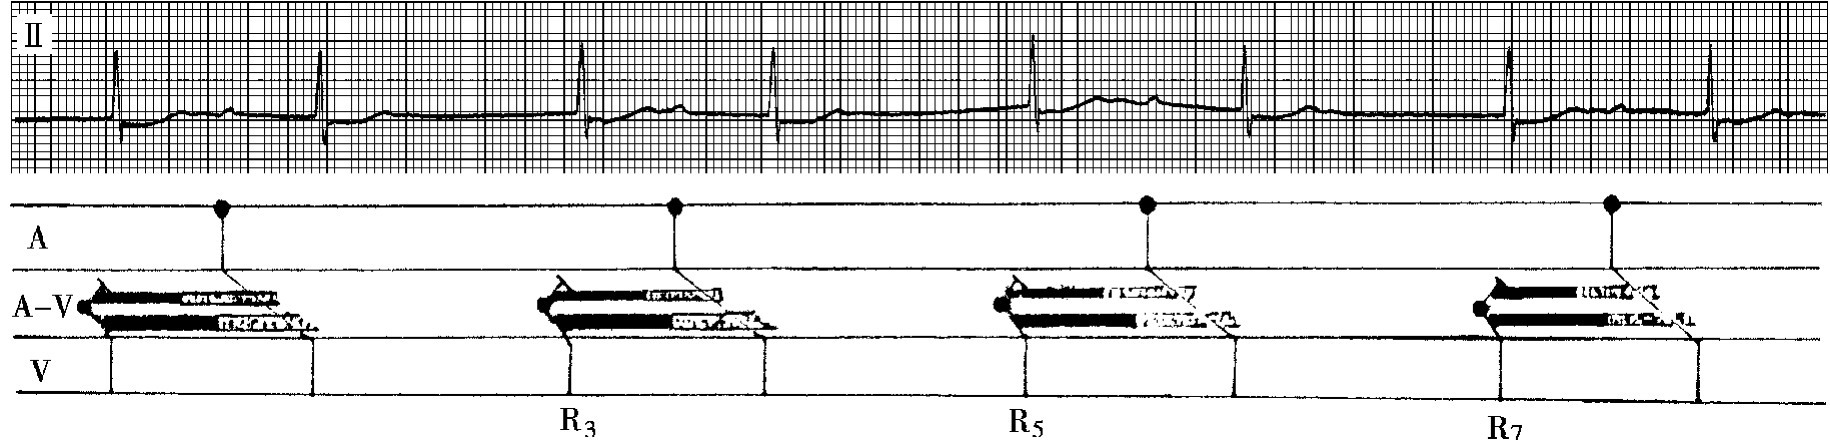

5.隐匿性交界性夺获 窦性心律、房室交界性心律或双重性交界性心律所形成的不完全性房室分离时,如发生心室夺获,高位起搏点的激动在房室交界区内发生隐匿性下传,虽未传到心室,但已提前兴奋了交界区节律点的激动,可使预期出现的交界性激动延迟出现,此种现象称为隐匿性交界性夺获(图43-6)。

(二)逆行性隐匿性房室传导的心电图表现 逆行性隐匿性房室传导指室性或交界性激动在房室交界区内逆向隐匿性传导,亦称室房隐匿性传导。其心电图特点为:

1.期前收缩伴完全性代偿间期 室性激动沿房室传导途径逆向上传,虽未能到达心房,产生逆行P波,但在房室交界区产生一次新的不应期,此时随后下传的窦性激动若遇上此期前收缩的绝对不应期,则不能下传,形成完全的代偿间歇(图43-7)。

img752

图43-6 隐匿性交界性夺获

图示窦性心律与交界性心律之间形成的干扰性房室脱节。第5个心房激动(P波埋没于QRS波群内)下传至交界区产生隐匿性夺获,提前释放交界区节律点的激动,致使交界性周期后移,第6个QRS波群因而延迟出现

img753

图43-7 室性期前收缩伴完全性代偿间期

2.插入性期前收缩后P-R间期延长 插入性室性异位激动逆行上传,在房室交界区产生不应期,随后下传的窦性激动恰遇此期前收缩所形成的相对不应期,传导延缓,出现P-R间期延长(图43-8)。

img754

图43-8 室性异位激动引起继后的P-R间期延长

第2个QRS波群为间位性室性期前收缩,第2个期前收缩发生逆行性隐匿房室传导,使房室交界区产生新的不应期,当窦性激动下传时,恰遇交界区处于相对不应期,因而P-R间期延长